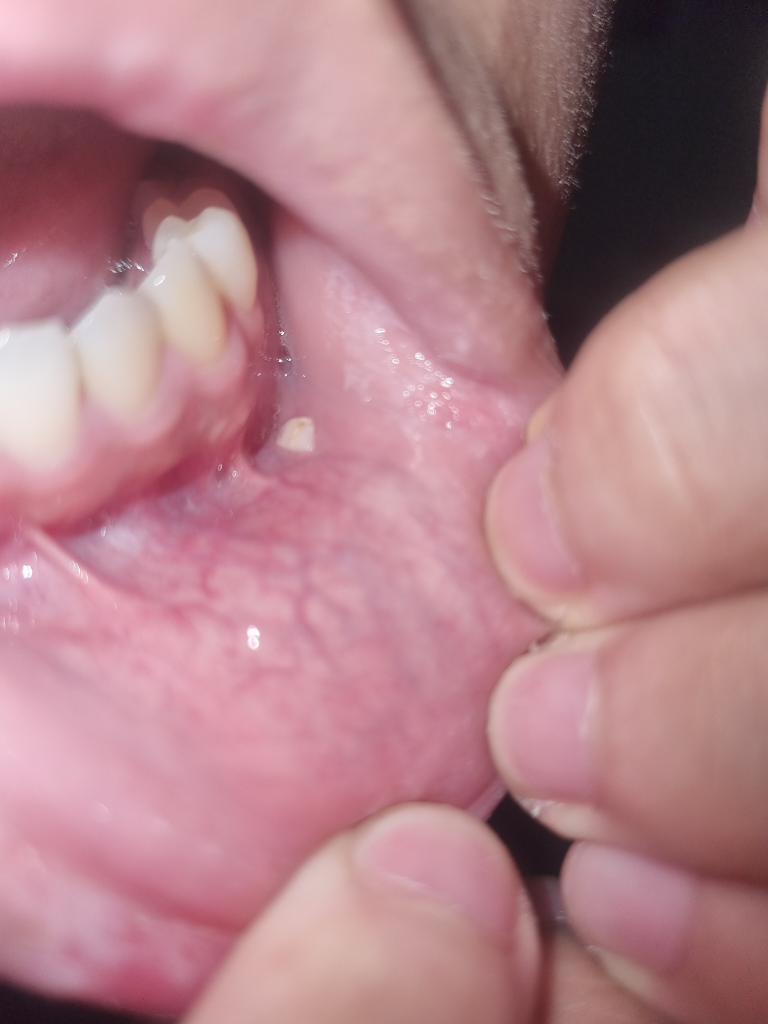

신경치료 이후 생긴 것 같은데 이게 어떤건가요?

얼음을 먹다 이가 부서져서 신경치료를 하고 왔다는데 이후 잇몸 아래에 하얀게 생겼다고 합니다. 면봉으로 만져봐도 잘 안움직이는 것 같다는데 이게 뭘까요? 방치하면 될까요?

신경치료는 부분마취로 진행했다고 합니다.

치아의 조각이거나 마취때문에 잇몸에 눌려서 그럴수도 있습니다. 크게 문제가 잇는건 아닌거 같으니 걱정하지 않으셔도 될것같습니다.